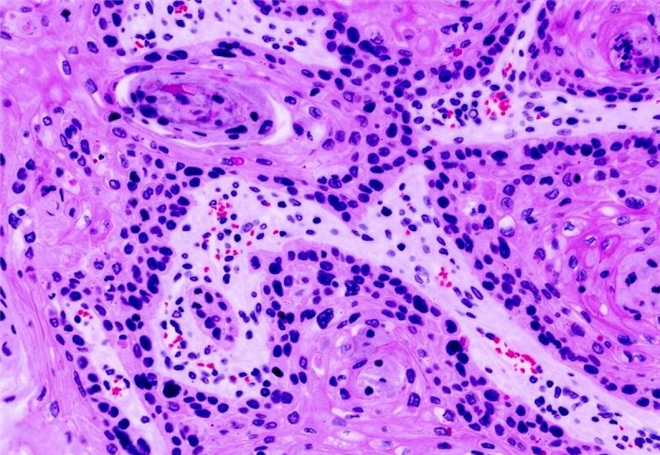

这是标准的着色组织切片样本。它被称为H&E样本,而且被病理学家用于基本的癌症诊断。这份特殊的样本源于患癌的肺部组织。这个样本尚未作出疾病标识,但是病理学家仍然能够通过观察细胞的形状和排列,识别出组织中的癌症特征。如果你仔细观察,每个细胞核都呈现暗紫色,恶性肿瘤细胞块呈现淡粉色,血管中的红血球呈现亮粉红色。